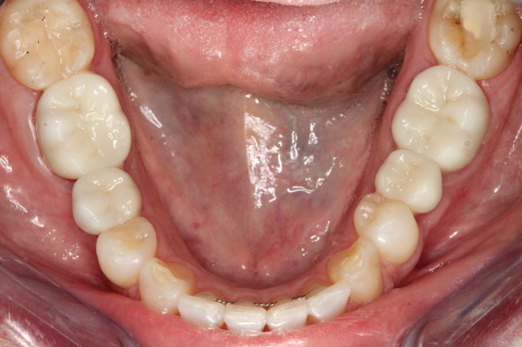

Fig 22. 12 weeks postoperatively.

Figure 22

Sutures were removed 2 weeks after surgical implant placement, and the patient was instructed to continuously wear his Essix-style retainer for 12 weeks. The retainer was worn while eating during the 12-week period. The patient returned at 12 weeks for soft-tissue and implant-bone evaluation (Figure 22). At this appointment, minimal lingual soft-tissue manipulation was performed by gingival abrasion to the keratinized soft tissue and an aluminum chloride gel was placed.